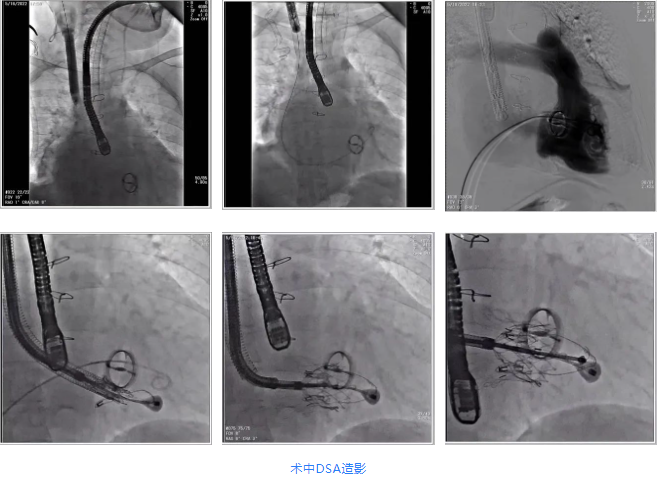

根據(jù)術(shù)前評估結(jié)果,郭應(yīng)強教授團隊為患者量身定制了手術(shù)策略,決定使用LuX-Valve Plus經(jīng)血管三尖瓣置換系統(tǒng)開展手術(shù)治療。手術(shù)在全麻下進行,采用經(jīng)右側(cè)頸靜脈入路,在經(jīng)食道超聲和DSA的指引下調(diào)整輸送器角度以達到正確位置,勾住前瓣后逐步釋放盤片,盤片打開后順利扎針,最終完成瓣膜植入,輸送器撤出。術(shù)后超聲提示人工三尖瓣同軸性良好,瓣架固定牢靠,無反流和瓣周漏,術(shù)后三尖瓣平均跨瓣壓差為1 mmHg。